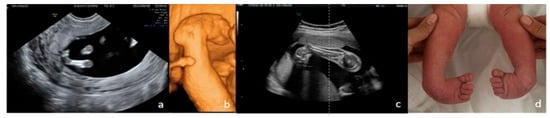

From Diagnosis to Decision—Fetal Limb Abnormalities

by Andreea Florentina Stancioi-Cismaru, Razvan Grigoras Capitanescu, Mihaela-Simona Naidin, Cristian Constantin, Marina Dinu, Florin Burada, Oana Sorina Tica, Mihaela Gheonea, Bianca Catalina Andreiana, Razvan Cosmin Pana and Stefania Tudorache

J. Clin. Med. 2026, 15(2), 486; https://doi.org/10.3390/jcm15020486 - 8 Jan 2026

Background/Objectives: Our aim was to investigate the diagnostic accuracy of prenatal ultrasound (US) in fetal limb abnormalities. As a secondary target, we wanted to correlate various predictors for the diagnosis accuracy. Methods: We prospectively enrolled cases with routine prenatal US performed in five [...] Read more.

Background/Objectives: Our aim was to investigate the diagnostic accuracy of prenatal ultrasound (US) in fetal limb abnormalities. As a secondary target, we wanted to correlate various predictors for the diagnosis accuracy. Methods: We prospectively enrolled cases with routine prenatal US performed in five participating centers. Subsequently, we selected and processed all cases with limb abnormalities: suspected, diagnosed, and missed on the prenatal diagnosis scans. We collected data on the type of anomaly, the US equipment and probes used, the operator’s expertise, the gestational age at the diagnosis, the length of the examination, and the use of US reporting form. SPSS 22.0 software was applied to perform the analyses using non-parametric statistical methods. Associations between categorical variables were evaluated using Fisher’s exact test and Chi-square tests. For correlations between the gestational age and the anomaly severity, we used Spearman’s rank-order correlation. Predictive performance of operator- and scan-related variables for diagnostic accuracy was assessed using receiver operating characteristic (ROC) curve analysis, with area under the curve (AUC) estimates, standard errors (SE), confidence intervals (95% CI), and p-values reported. Results: Our data showed that most US examinations were performed as part of routine screening (79.7%), and the most frequent anomaly diagnosed was clubfoot. Operators’ expertise demonstrated the highest predictive performance, while technical parameters—scan duration (AUC = 0.20, p = 0.1188) and US equipment (AUC = 0.30, p = 0.3478)—did not significantly predict diagnostic accuracy. Conclusions: The overall diagnostic accuracy of prenatal US was 85.5%. Our findings indicate that diagnostic performance is driven primarily by operator expertise and training, rather than by gestational age at scan and technical parameters. Full article

Show Figures

Figure 1